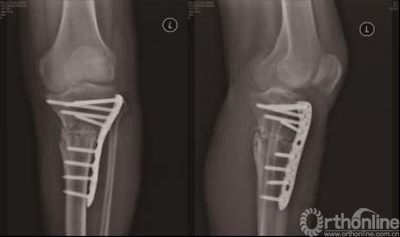

3.个性化导航模板在人工全膝关节置换中的实验研究

在Imageware13.0软件中建立局部三维坐标系,确定行股骨远端截骨的导航定位针孔所在的平面,再根据截骨模块两侧对称的固定针孔间的距离,垂直于确定的导航定位针孔所在的平面进行平行点云截面操作,通过点云拟合操作创建出两条直线,获得股骨远端截骨导航定位孔的位置(图11)。在Imageware13.0中基于股骨机械轴线及股骨外科髁上轴,建立局部参考坐标系,得到模块两条固定针进针的中心直线,即为导航定位孔方向(图12)。按照在Geomagic11.0中确定的胫骨截骨参照点及对截骨模板的测量,确定胫骨截骨导航定位针孔所在平面(图13)。调整该平面后倾角度,获得胫骨近端导航模板定位孔(图14)。根据整个下肢髋-膝-踝关节MRI数据建立股骨与胫骨机械轴线,按照实际膝关节的表面解剖形态设计模板的贴合面,确定导航管的位置与方向,从而设计出股骨、胫骨截骨定位的个体化导航模板,进行模拟截骨(图15)。

表一

研究表明,膝关节导航模板具有很高的股骨远端和胫骨近端截骨精确性和假体旋转轴线定位的准确性,为TKA提供了一种新的辅助方法。能够获取准确的下肢机械轴线、股骨远端假体旋转轴线、假体位置,同时也有效的减少了术后并发症,近期临床效果值得肯定。